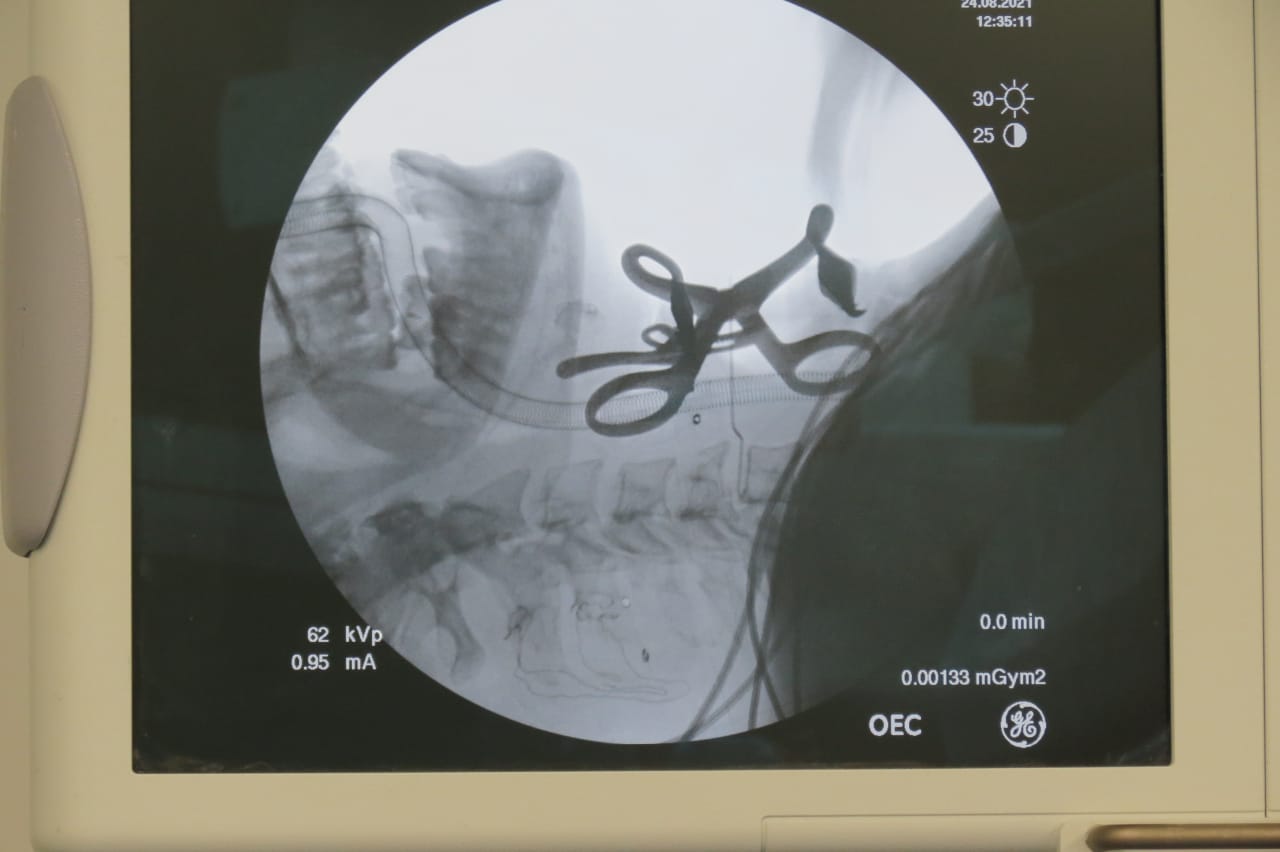

وأضافت الهيئة، أنه على الفور تم حجز المريض بالرعاية المركزة بقسم جراحة المخ والأعصاب داخل المستشفى، وتجهيزه وإدخاله غرفة العمليات وتخديره بواسطة المنظار الجراحي المتصل بالفيديو للحفاظ على ثبات الفقرات المكسورة، وإجراء التدخلات الجراحية اللازمة له حيث تمت إزالة الفقرة الخامسة العنقية المكسورة، ورفع الضغط عن الحبل الشوكي والأعصاب باستخدام الميكروسكوب الجراحي، وتركيب بديل للفقرة المكسورة من مادة التيتانيوم الطبي وتثبيتها بواسطة شريحة ومسامير، مؤكدة استقرار الحالة الصحية للمريض وتلقيه العلاج الطبيعي والدوائي الآن تحت ملاحظة ورعاية المستشفى.